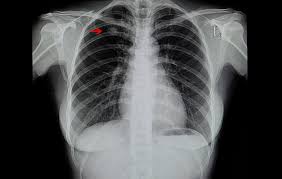

"폐결절(lung nodule)"은 폐 조직 내에서 직경 3cm 이하의 원형 또는 타원형 덩어리를 말합니다. 일반적으로 엑스레이나 CT 촬영에서 발견되며, 단독으로 존재하는 경우가 많지만 여러 개 나타날 수도 있습니다.

폐결절 진단은 주로 영상검사와 조직검사를 통해 이루어집니다.

- 영상 검사

- 흉부 X-ray: 초기 발견 용이, 해상도 낮음

- CT(컴퓨터단층촬영): 크기, 모양, 경계, 칼슘 침착 확인